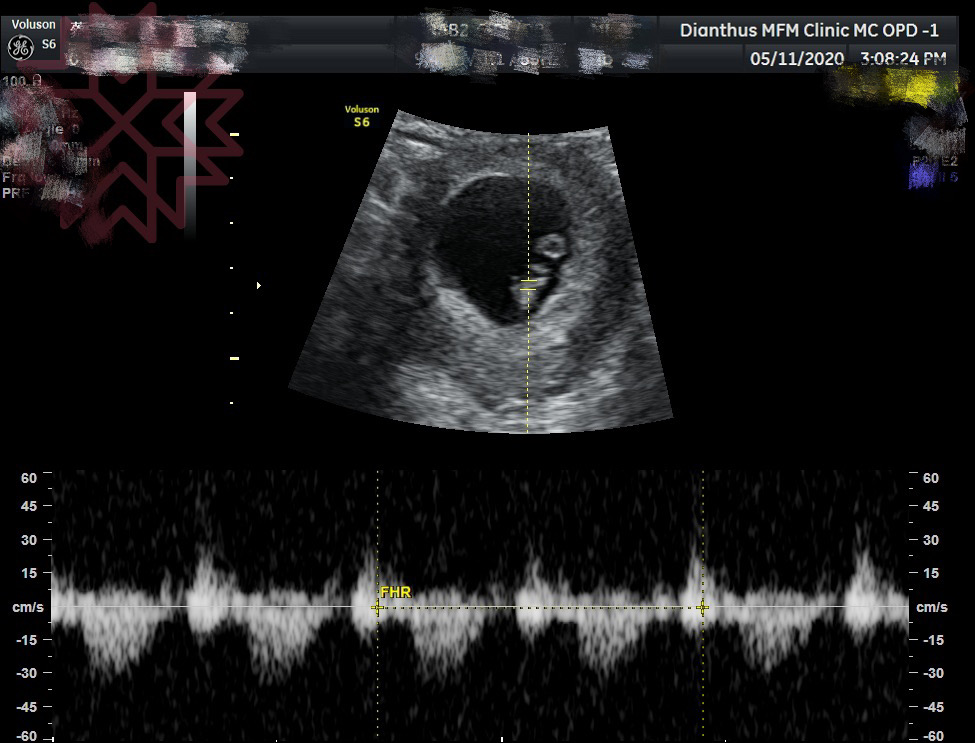

噗通噗通…我聽到了世界上最美的聲音

第8週左右的產檢時,我們看到、也聽到了二寶的心跳。薑再老好像還是不會辣,因為我聽了還是好感動、眼淚又快奪框而出,因為我知道寶寶目前一切都好。